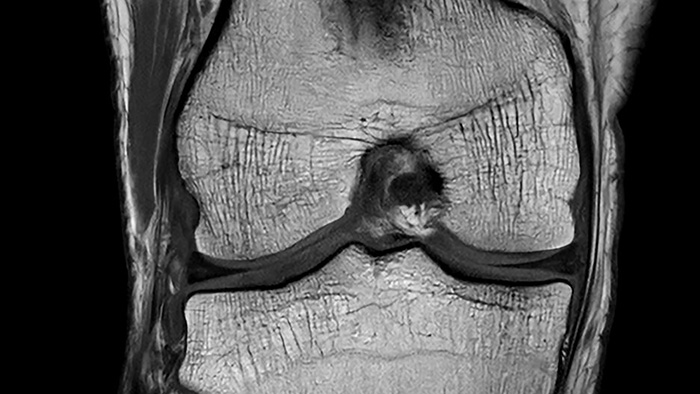

De nieuwste SmartSpeed Precise [1]-technologie verhoogt de productiviteit nog verder, waardoor scans tot drie keer sneller kunnen worden uitgevoerd [7] en de scantijd aanzienlijk wordt verkort terwijl de uitzonderlijke beeldkwaliteit behouden blijft. De kern van SmartSpeed Precise is de dual AI-engine, die zorgt voor een verbetering van 80% in de scherpte van de beelden [8], waardoor de visualisatie wordt verbeterd voor betrouwbaardere en nauwkeurigere diagnoses. Deze krachtige combinatie van snelheid en precisie zorgt ervoor dat radiologen subtiele afwijkingen duidelijker kunnen detecteren, wat uiteindelijk leidt tot betere patiëntresultaten. De nieuwe release van Philips – MR Workspace R12 [6] – introduceert een ‘zero-click’-workflow [9], die het gehele beeldvormingsproces naadloos begeleidt, van het starten van de scan tot het genereren van rapporten. Door handmatige handelingen te verminderen en de efficiëntie te optimaliseren, stelt MR Workspace R12 [6] radiologieafdelingen in staat de patiëntdoorstroming te verbeteren en achterstanden terug te dringen, waarmee tegemoet wordt gekomen aan de toenemende vraag naar snellere en nauwkeurigere beeldvorming. Een belangrijke innovatie binnen MR Workspace R12 [6] is de door AI aangestuurde SmartExam-functie, die 80% van de MR-procedures automatiseert [10], door werkzaamheden te stroomlijnen en beeldvormingsworkflows te standaardiseren.

Andere baanbrekende innovaties zijn onder andere Smart Reading [4], de eerste oplossing in de industrie die cloudgebaseerde, door AI aangestuurde kwantitatieve rapportage naadloos [11] integreert. Smart Reading maakt gebruik van geavanceerde AI-platformen zoals icobrain (icometrix) voor neurologie – inclusief detectie van de ziekte van Alzheimer – en QP-Prostate (Quibim) voor geavanceerde diagnose van prostaatkanker. Door objectieve, zeer betrouwbare diagnoses te leveren, maken deze zero-click AI-oplossingen [9] gestroomlijnde, op data gebaseerde besluitvorming mogelijk voor artsen. Met MR Workspace R12 [6], SmartSpeed Precise [1] en Smart Reading [4] blijft Philips de grenzen van AI in MRI verleggen om de efficiëntie, nauwkeurigheid en toegankelijkheid van diagnostische beeldvorming te vergroten en tegelijkertijd de weg vrij te maken voor de toekomst van autonome MR-scanning.